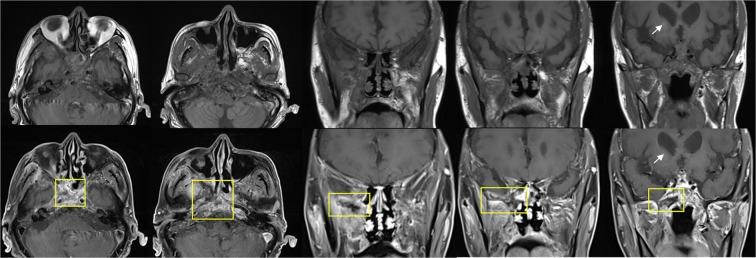

Acute invasive fungal rhinosinusitis (AIFRS) can spread beyond the sinonasal cavity. It is necessary to analyze the association between the specific site involved in the extrasinonasal area and the survival rate to predict patient prognosis. We investigated 50 patients who had extrasinonasal lesions on preoperative gadolinium (Gd)-enhanced magnetic resonance imaging (MRI) scan and underwent wide surgical resection of AIFRS. The specific sites with loss of contrast enhancement (LoCE) on Gd-enhanced MRI were analyzed for AIFRS-specific survival rate. The most common underlying disease was diabetes mellitus followed by hematological malignancy. The most common symptoms were headache and facial pain. Seven patients (14.0%) expired because of AIFRS progression. Poor prognosis was independently associated with LoCE at the skull base on preoperative MRI (HR = 35.846, P = 0.004). In patients with AIFRS extending to the extrasinonasal area, LoCE at the skull base was an independent poor prognostic factor.

急性侵袭性真菌性鼻-鼻窦炎(AIFRS)可扩散至鼻窦腔以外。有必要分析鼻窦外受累特定部位与生存率之间的关系,以预测患者的预后。我们研究了 50 名术前钆增强磁共振成像(MRI)扫描显示鼻窦外病变并接受 AIFRS 广泛手术切除的患者。对 Gd 增强 MRI 上出现对比剂丢失(LoCE)的特定部位进行分析,以评估 AIFRS 特异性生存率。最常见的潜在疾病是糖尿病,其次是血液恶性肿瘤。最常见的症状是头痛和面部疼痛。7 名患者(14.0%)因 AIFRS 进展而死亡。术前 MRI 上颅底的 LoCE 与不良预后独立相关(HR = 35.846,P = 0.004)。在 AIFRS 扩散至鼻窦外的患者中,颅底的 LoCE 是独立的不良预后因素。